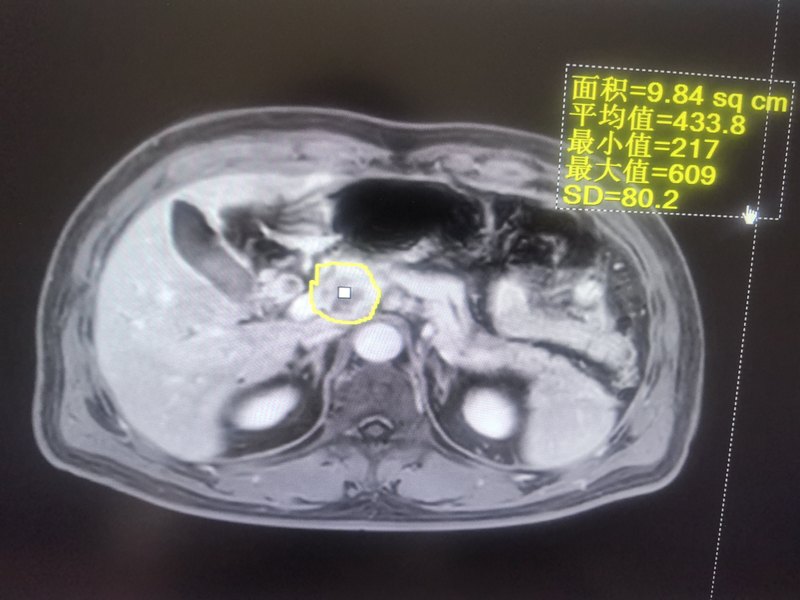

上圖是一個(gè)膽管癌患者,術(shù)前7,8,9,12,13組淋巴結(jié)轉(zhuǎn)移,術(shù)前總膽紅素70,做了膽管癌根治術(shù)術(shù)中清掃淋巴結(jié)膽管癌的特點(diǎn):早期有淋巴結(jié)治療,大部分患者沒(méi)有特效靶向藥,化療不敏感,手術(shù)治療是最好的治療措施。